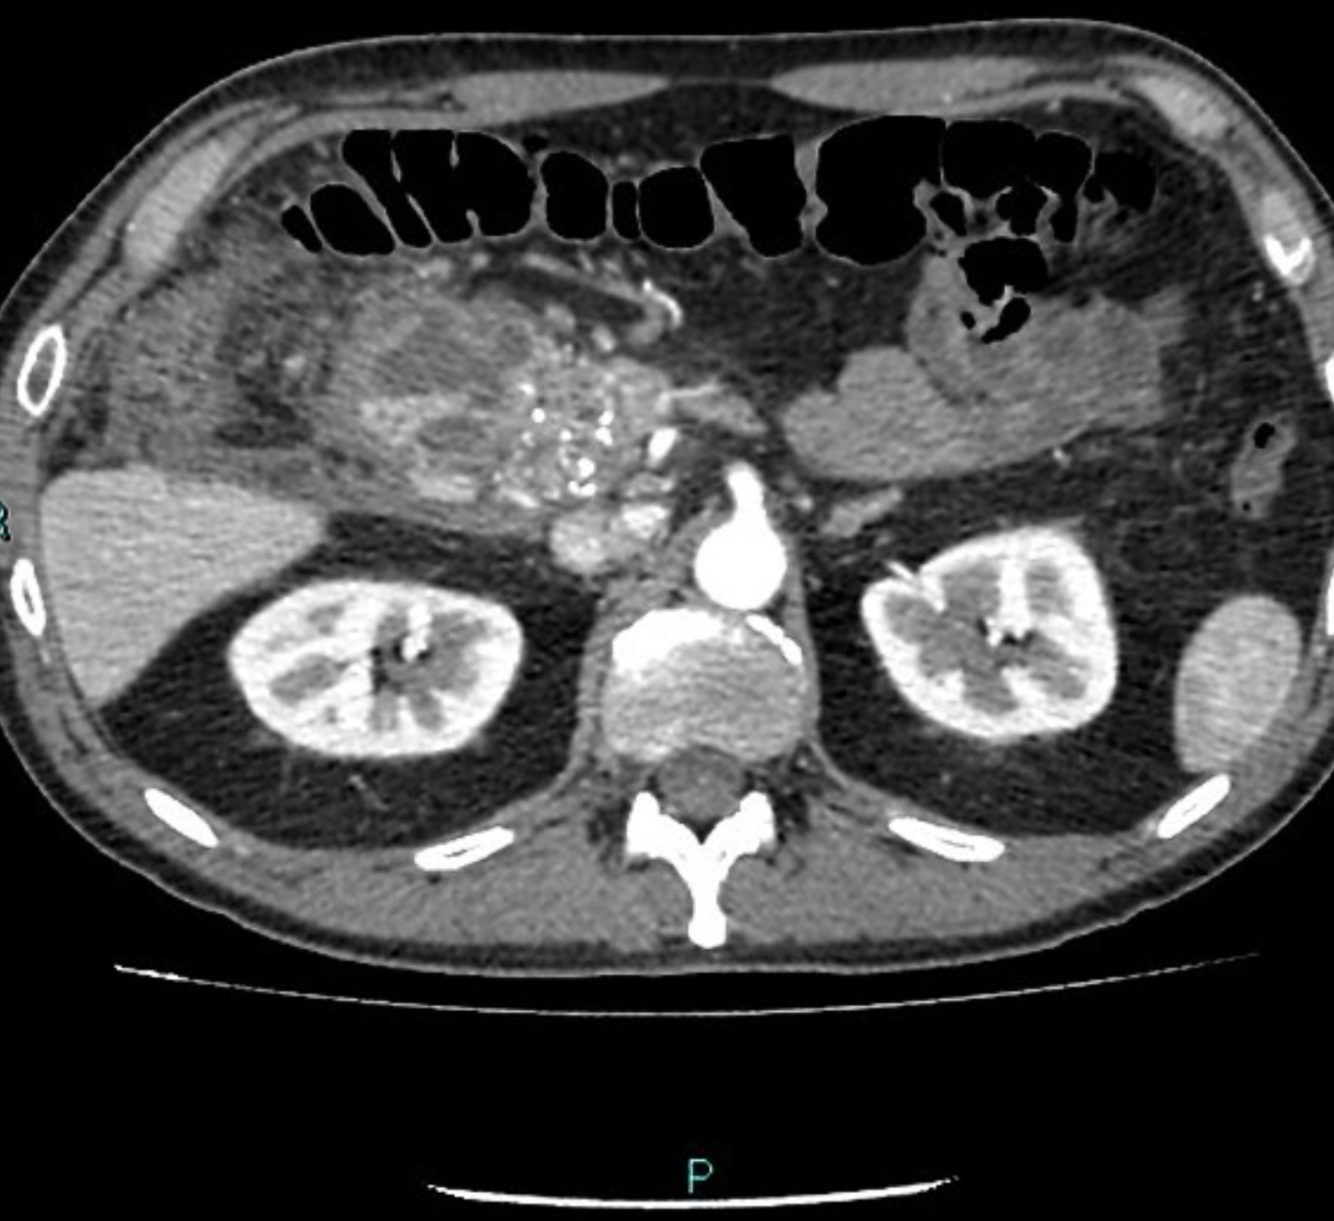

Complications of Chronic Pancreatitis

Generalised atrophy of body and tail of the pancreas. Diffuse parenchymal calcification with main pancreatic duct dilated throughout its course with a beaded appearance reaching up to 10mm in diameter. Multiple intraductal calculi are present, the largest measuring 10 mm in the pancreatic head. This stone is obstructing the main pancreatic duct resulting in ductal dilatation. No hypoenhancing pancreatic parenchymal lesions. No peripancreatic fat stranding or localised collections. No radio-opaque stones in the gallbladder, cystic duct, or common bile duct. No intrahepatic biliary duct dilatation.

Case Discussion

When presenting with an episode of abdominal pain, this patient underwent an ultrasound of the abdomen which revealed features of chronic calcific pancreatitis. However, due to the suboptimal acoustic window, a CT scan was recommended to rule out any pancreatic inflammation or neoplasm. The chronic inflammatory changes result in reduction in volume of pancreatic parenchyma with only a ghost of the gland remaining in the latter stages. These patients are more prone for neoplasms and have to be watched closely.